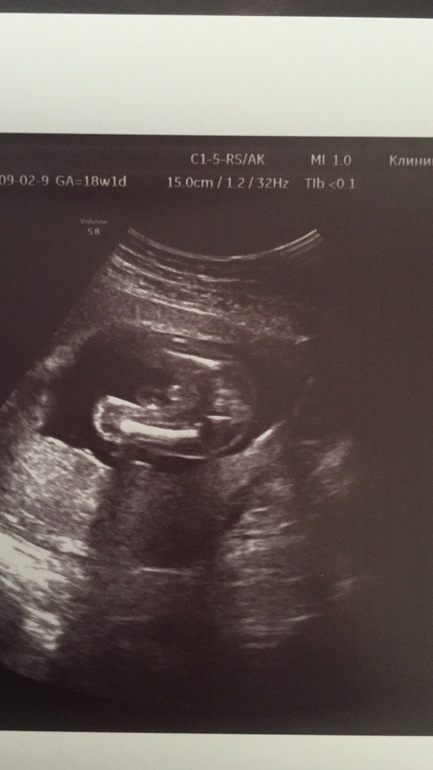

УЗИ, КТГ, доплерВ общем сегодня ходила на УЗИ, что то второй день тянет живот и поясницу, а мы на море собрались. Думаю надо посмотреть, до скрининга ещё почти две недели. Вроде все хорошо, немного тонус и тайна раскрыта! У нас будет сынок! Фото под кат...

Фото нашего достоинства, сначала оно, а дальше немного пуповину видно, но врач сказал сомнений нет, да я и сама все разглядела сразу. Срок 18 недель.